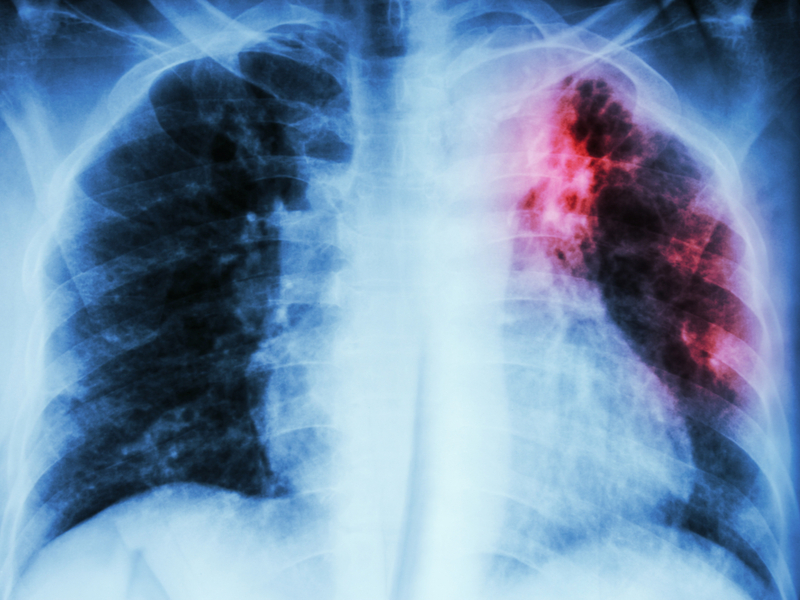

Drug discovery firm Evotec, owner of the API manufacturer Aptuit, is a member of the Project to Accelerate New Treatments for Tuberculosis (PAN-TB) collaboration, which was launched formally on 27 February. This will aim to transform global action on TB, which causes more deaths than any other infectious disease, with 10 million new cases and 1.5 million deaths recorded in 2018.